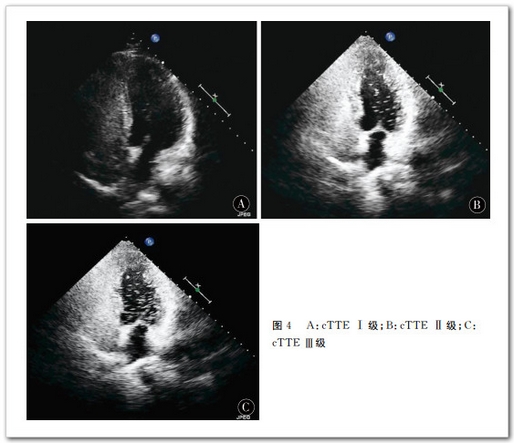

166 例 患 者 中 cTCD檢 測(cè) 出 RLS80 48.19%),cTTE 檢 測(cè) 出RLS68 40.96%),差異有統(tǒng)計(jì)學(xué)意義0.005)。cTCD靜息 狀 態(tài) 下 檢 測(cè) 出RLS2716.27%),Valsava動(dòng)作后檢測(cè)出RLS8048.19%)。Valsava動(dòng)作后 RLS檢出率明顯高于靜息狀態(tài)0.005)。cTTE靜 息 狀 態(tài) 下 檢 測(cè) 出 RLS2816.87%),Valsava動(dòng)作后檢測(cè)出 RLS6841.76%)。Valsava動(dòng)作后 RLS檢 出 率 明 顯 高 于 靜 息 狀 態(tài)0.005)。cTCD 半定量分級(jí)結(jié)果級(jí)少量分流2615.66%),級(jí)中量分流2615.66%),級(jí)大量分流2816.87%);cTTE半 定 量 分 級(jí) 結(jié) 果級(jí)少量分流2716.27%),級(jí)中量分流1911.45%),級(jí)大量分流2213.25%)。兩 種 檢 查 方 法 的 分 級(jí) 結(jié) 果 差 異 有 統(tǒng)計(jì)學(xué)意義Bowker檢驗(yàn)值14.818,=0.011),cTCDcTTE檢出 RLS級(jí)別高。